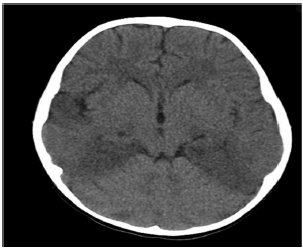

Paciente do sexo masculino de 47 anos dá entrada no pronto-socorro com quadro de febre alta de até 40 graus, há 3 dias, seguido por confusão mental e alterações de comportamento há 1 dia.

Familiares referem que o paciente em questão começou a esmurrar a parede sem propósito, além de ficar se encarando no espelho durante horas a fio.

Ao exame neurológico, agitado, Glasgow 14, sem déficits focais, mas com discurso desconexo. Realizada TC de crânio:

Realizado, ainda, exame de líquor, com os seguintes achados: glicose 55, proteínas 70, células 52 (predomínio linfo-mono), bacterioscópio negativo.

A conduta adequada para o manejo desta condição é